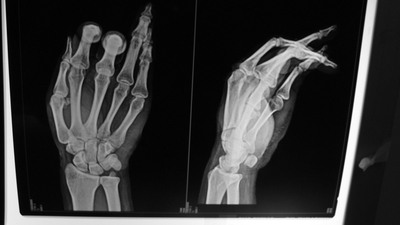

时隔17小时,手指再植奇迹存活

54岁的毋先生在家用锯子切割木块时,一不小心锯片弹起切断左手示指和中指,经过4个小时的再植术,最终毋先生的断指成功接上了